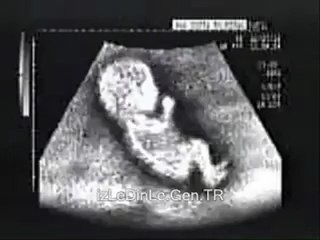

Anne karnındaki bebeğin cinsiyeti ultrasonla nasıl tespit edilir?

Acıbadem Fulya Hastanesi, Kadın Hastalıkları ve DoğumPerinatoloji Uzmanı Doç. Dr. Derya Eroğlu, Hamilelik üzerine soruları yanıtlıyor;br br "Anne karnındaki bebeğin cinsiyeti ultrasonla nasıl tespit edilir?"br br Acıbadem Sağlık Grububr www.acibadem.com.